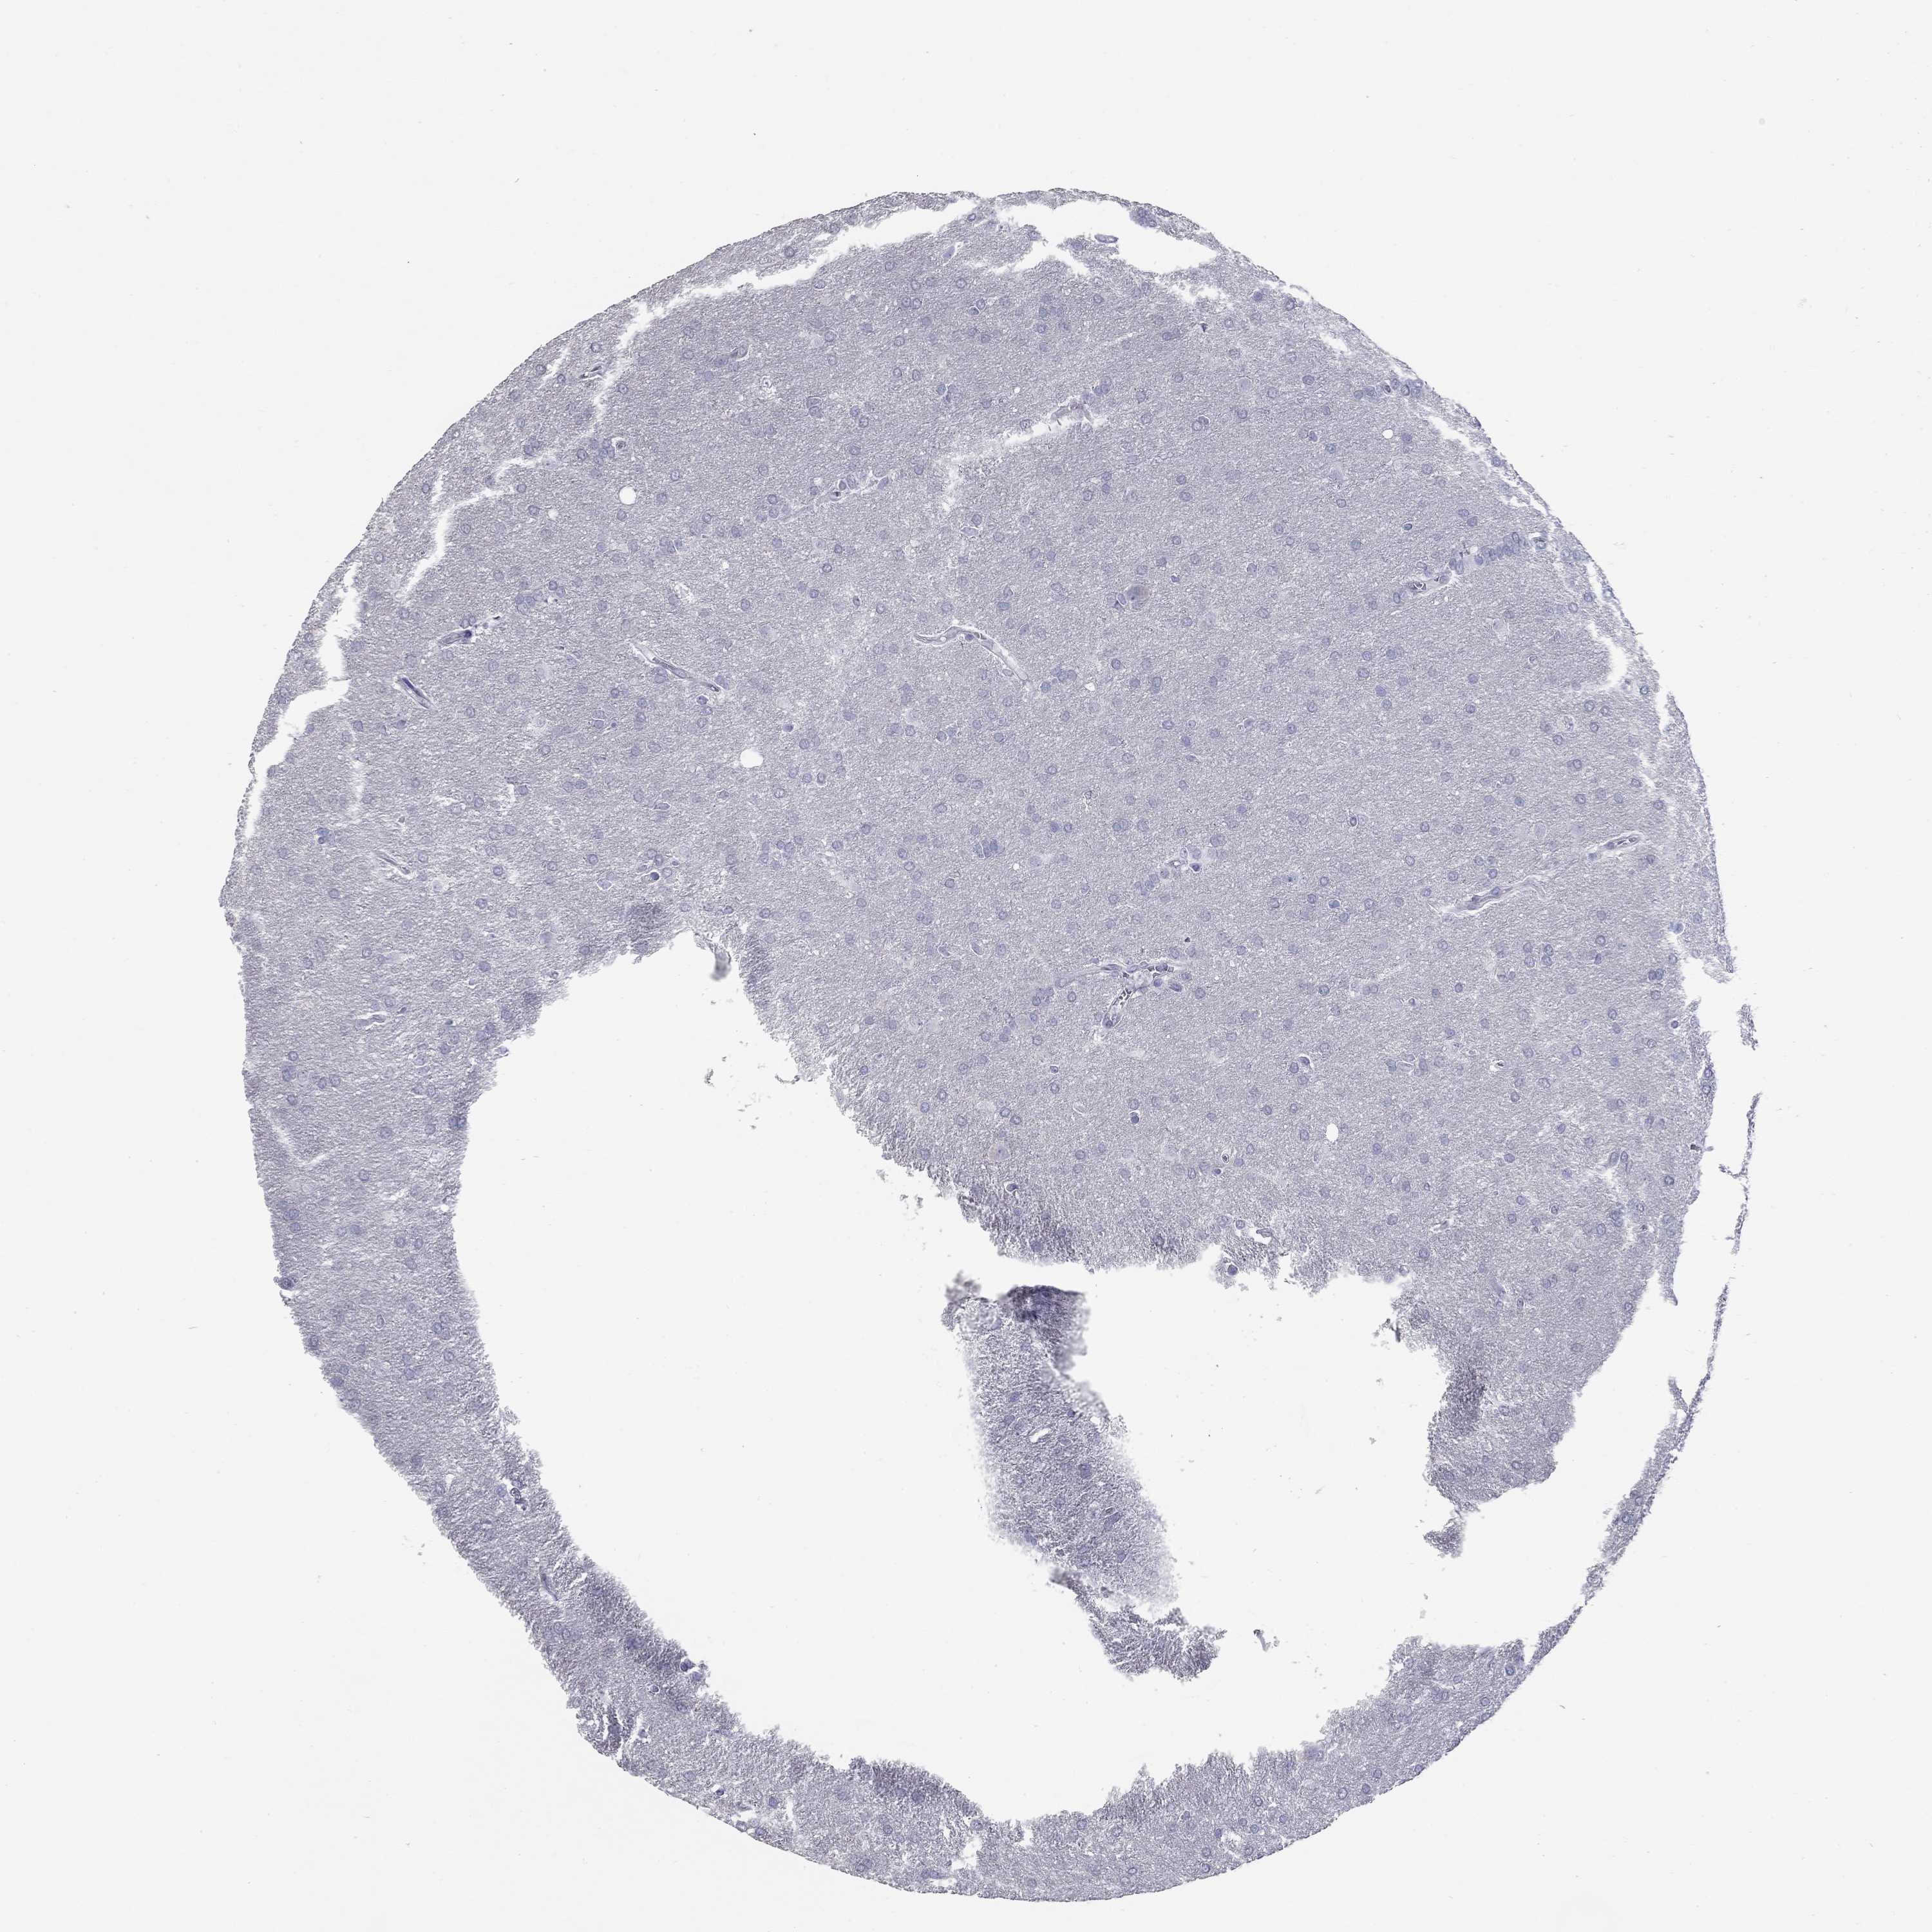

GLIOMA - Protein expressioni

A mouse-over function shows sample information and annotation data. Click on an image to view it in a full screen mode. Samples can be filtered based on level of antibody staining by selecting one or several of the following categories: high, medium, low and not detected. The assay and annotation is described here.

Note that samples used for immunohistochemistry by the Human Protein Atlas do not correspond to samples in the TCGA dataset.

Antibody stainingi

Antibody staining in the annotated cell types in the current human tissue is reported as not detected, low, medium, or high, based on conventional immunohistochemistry profiling in selected tissues. This score is based on the combination of the staining intensity and fraction of stained cells.

Each image is clickable and will lead to virtual microscopy that enables deeper exploration of all samples and also displays staining intensity scores, fraction scores and subcellular localization as well as patient and tissue information for each sample.

Antibody HPA014429

Staining

High

Medium

Low

Not detected

Intensity

Strong

Moderate

Weak

Negative

Quantity

>75%

75%-25%

<25%

None

Glioma, malignant, Low grade

Glioma, malignant, High grade

Glioma, malignant, NOS